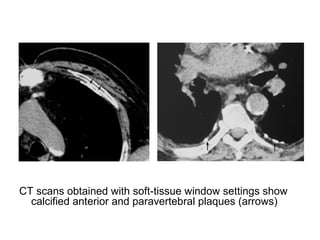

CT scans obtained with soft-tissue window settings show

calcified anterior and paravertebral plaques (arrows)